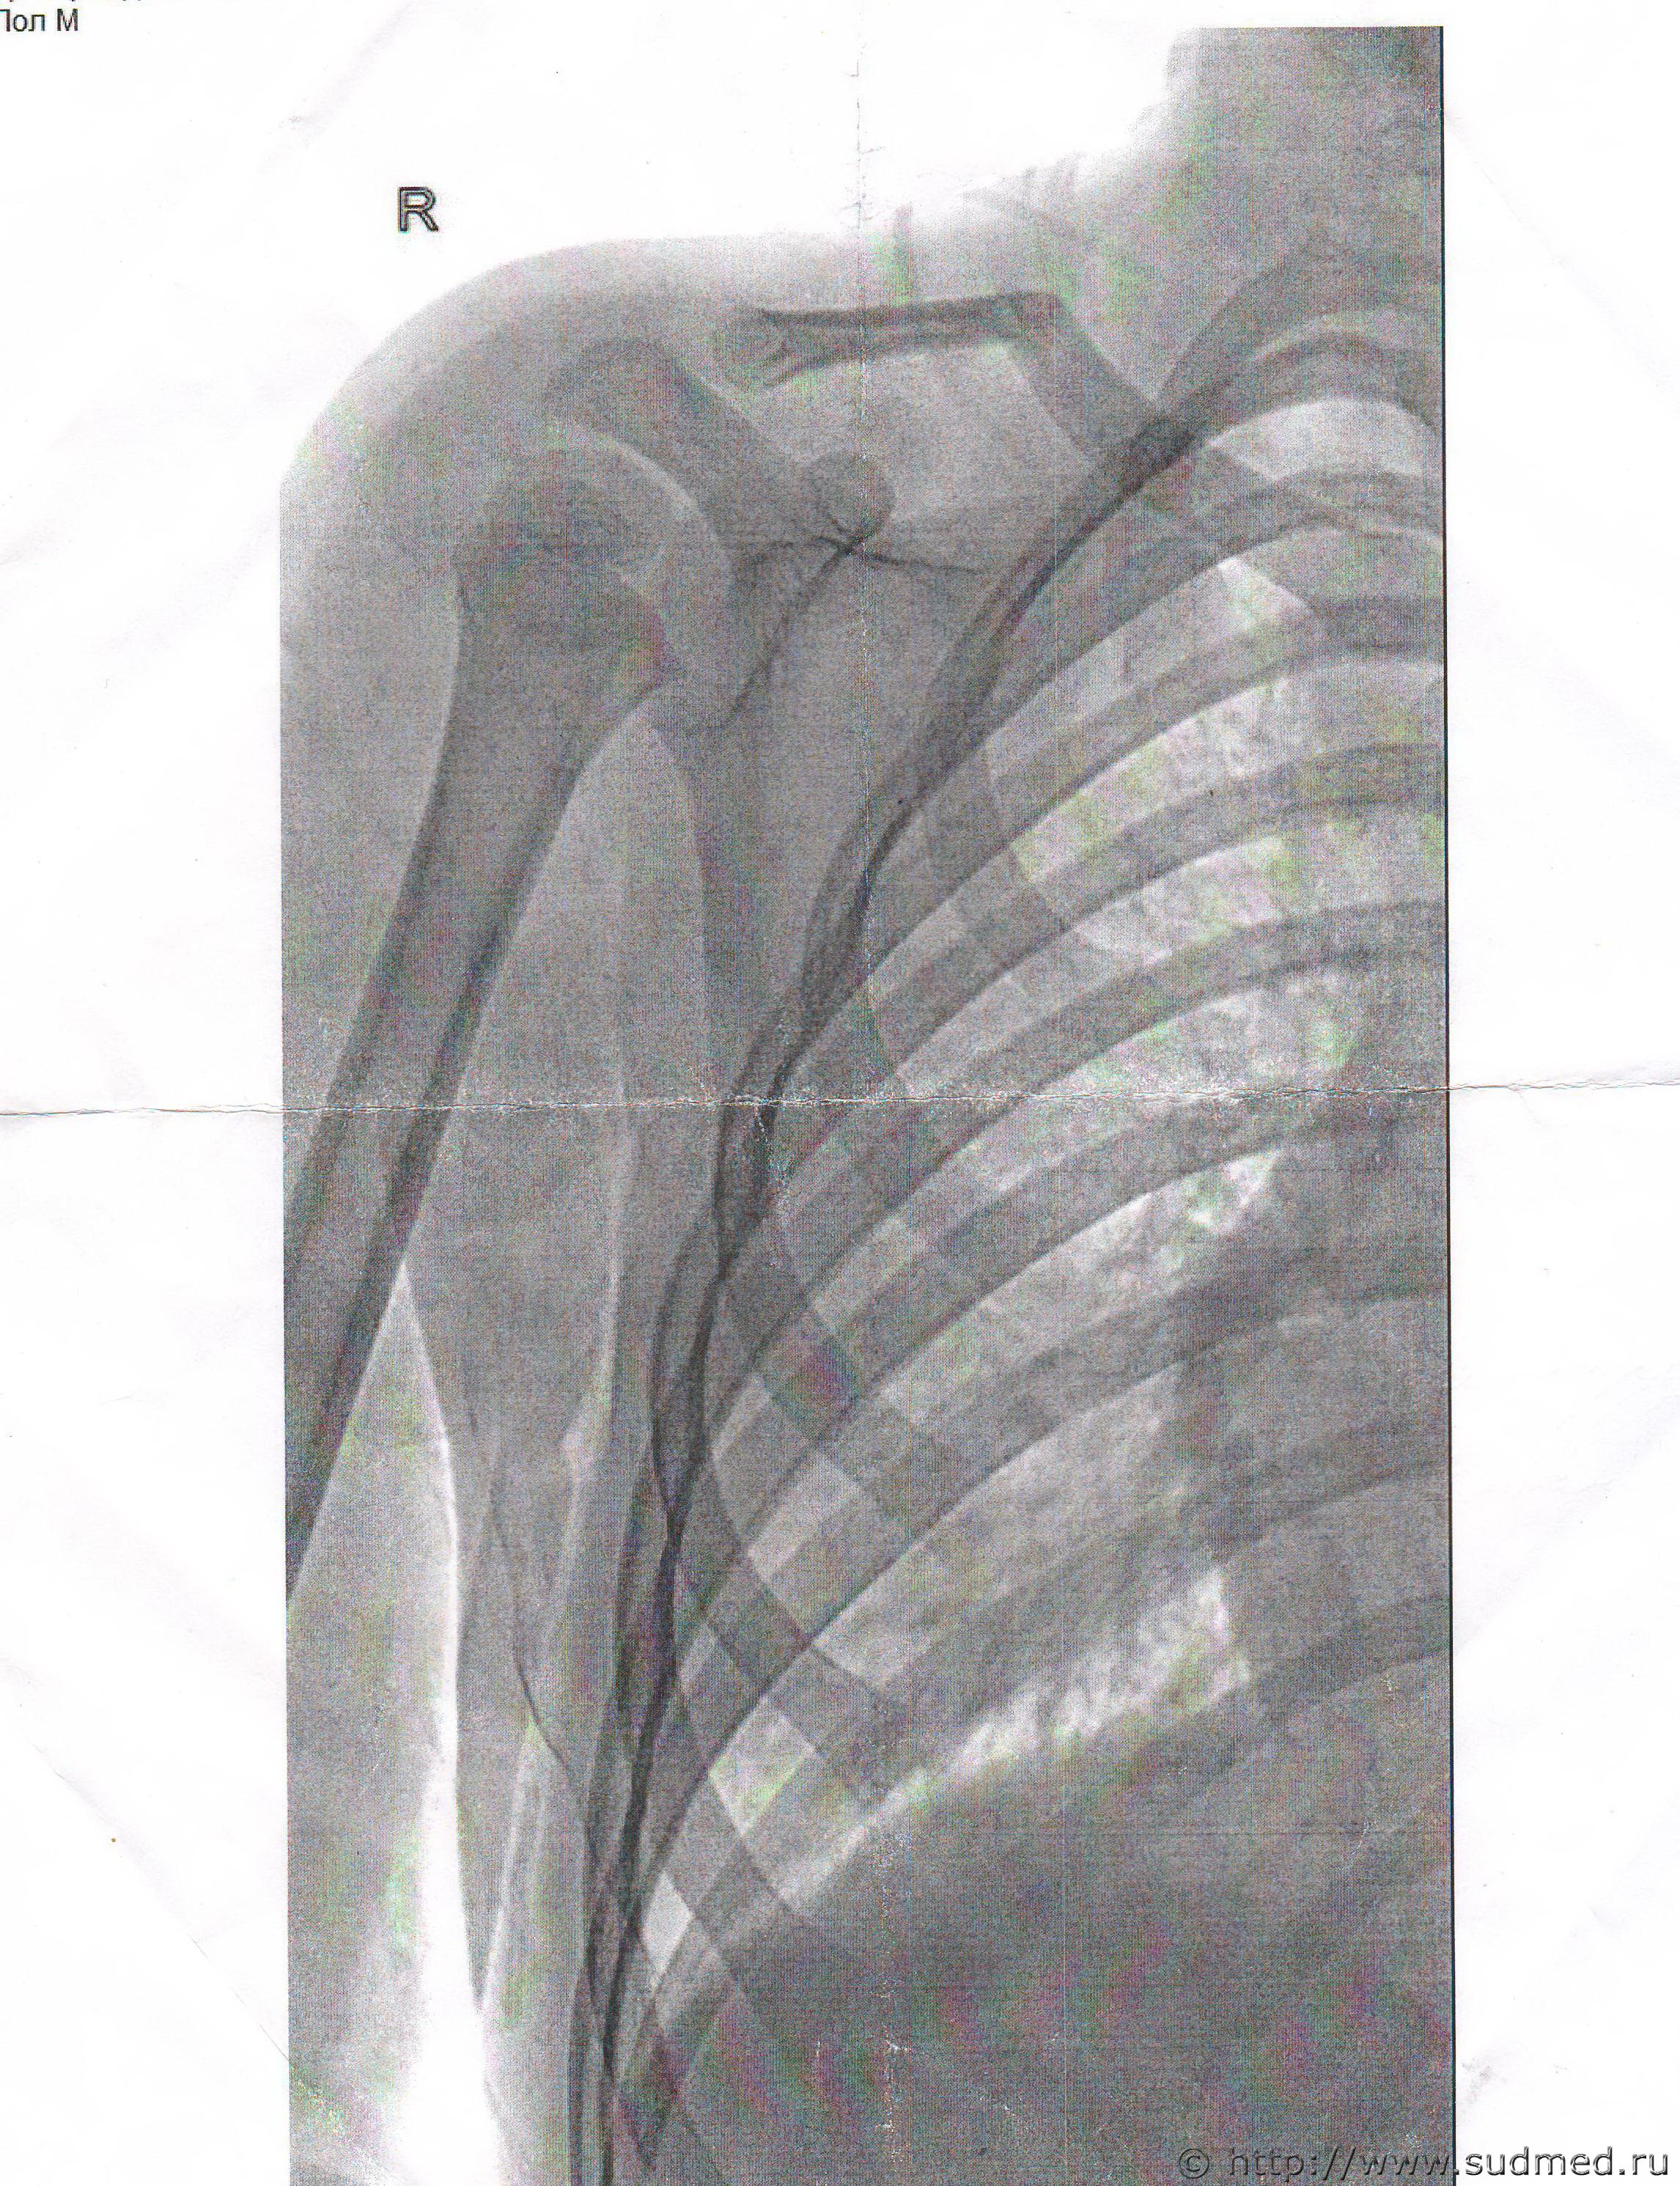

Могу рентген показать

Эскизы прикрепленных изображений

Судебная медицина - Прикрепленное изображение